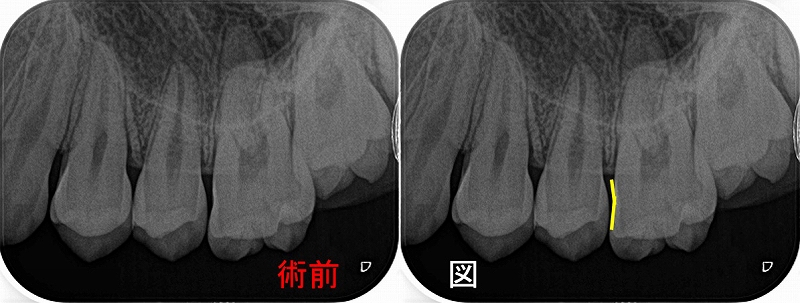

第二大臼歯に直接覆髄がしてありますが、根の方には大きな透過像(骨が溶けている場所)

第一大臼歯遠心根にもうっすら透過像あり。

綺麗に骨が出来上がってくれています!

また1本前の根尖病変に見えた歯の所見も落ち着いているように見えます。